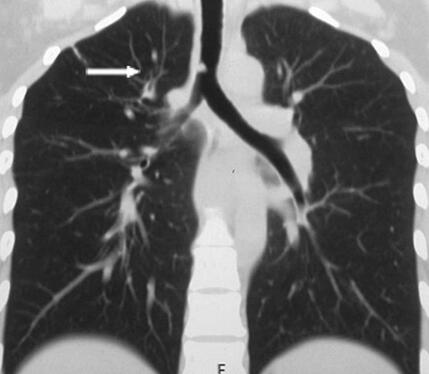

图1 2014年10月18日胸部CT

右肺上叶可见斑片、索条影,气管末端可见一结节样隆起(箭头),右主支气管明显狭窄